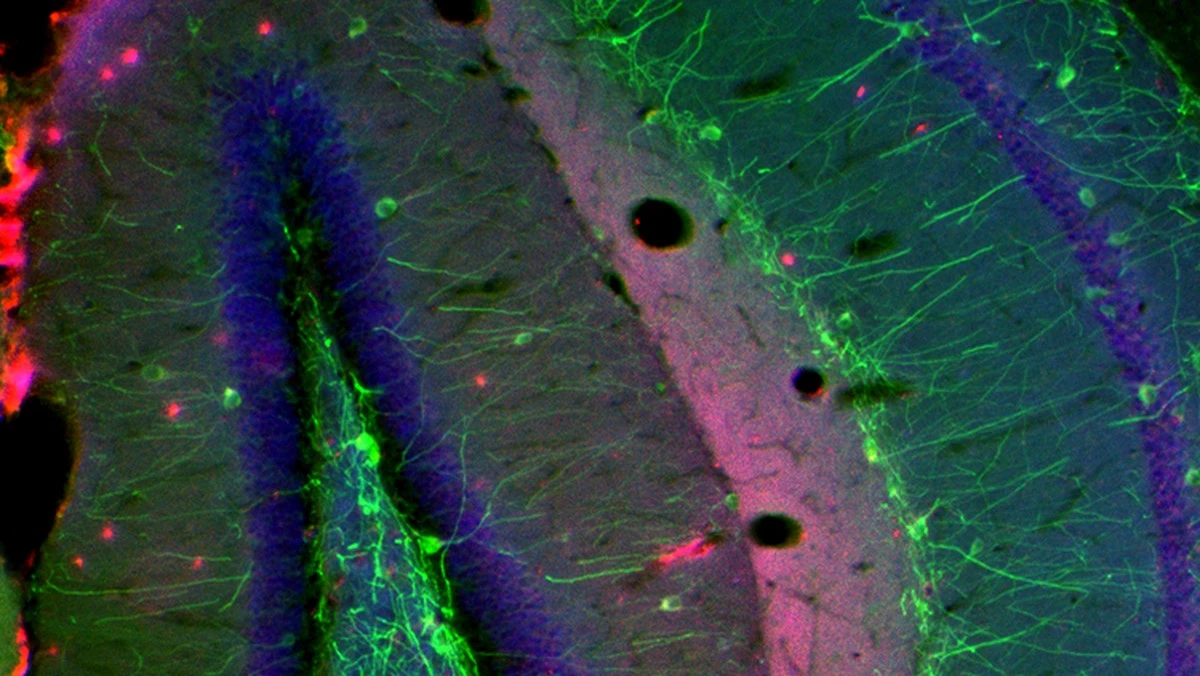

Možná si říkáte, že by se bakterie musely dostat do krve, aby se rozšířily po těle. Jenže tady je ten háček. Vědci zjistili, že tyto bakterie v krvi vůbec nebyly. Experimenty ukázaly, že mikroorganismy využívají vagus, neboli bloudivý nerv, jako přímou spojnici.

Představte si to jako tajný tunel pod městem, o kterém nikdo neví, dokud jím nezačnou proudit nezvaní hosté. Když vědci tento nerv u myší zablokovali, přítomnost bakterií v mozku se dramaticky snížila. To potvrzuje, že nervová soustava neslouží jen k přenosu signálů, ale i jako fyzická cesta.